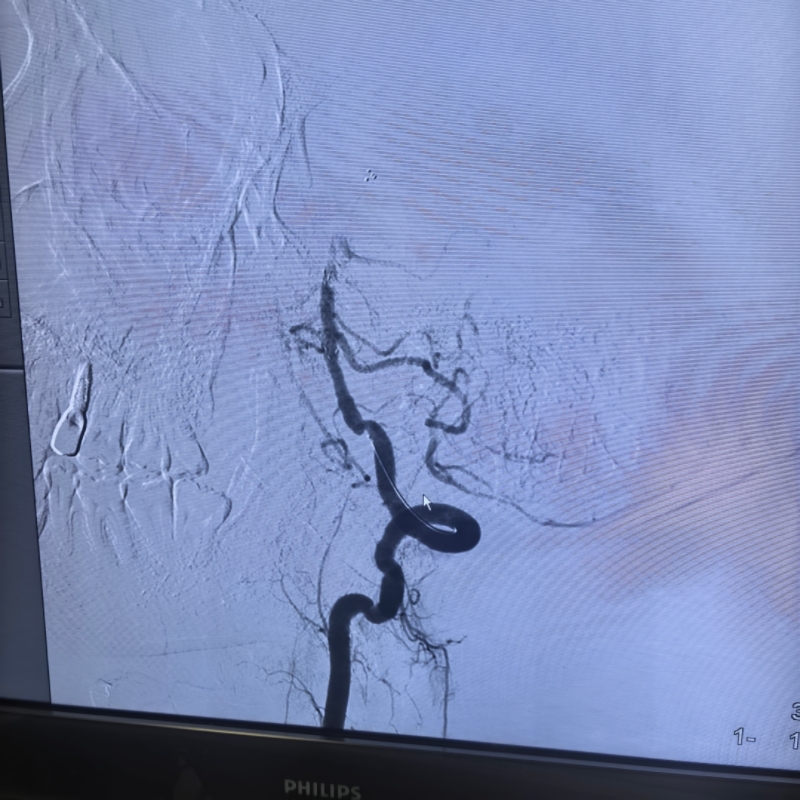

术中示专用颅内取栓支架卡住基底动脉血栓

“患者太年轻了,必须拼尽全力!”卒中中心团队傅新民主任、陈施吾医生、张慧医师迅速启动急诊取栓绿色通道。手术台上,医生凭借精湛的介入技巧,小心翼翼地操控导管,穿过纤细的椎动脉,精准抵达闭塞的基底动脉部位。随着器械缓缓推进,一团血栓被成功取出,原本堵塞的血管重新恢复通畅。